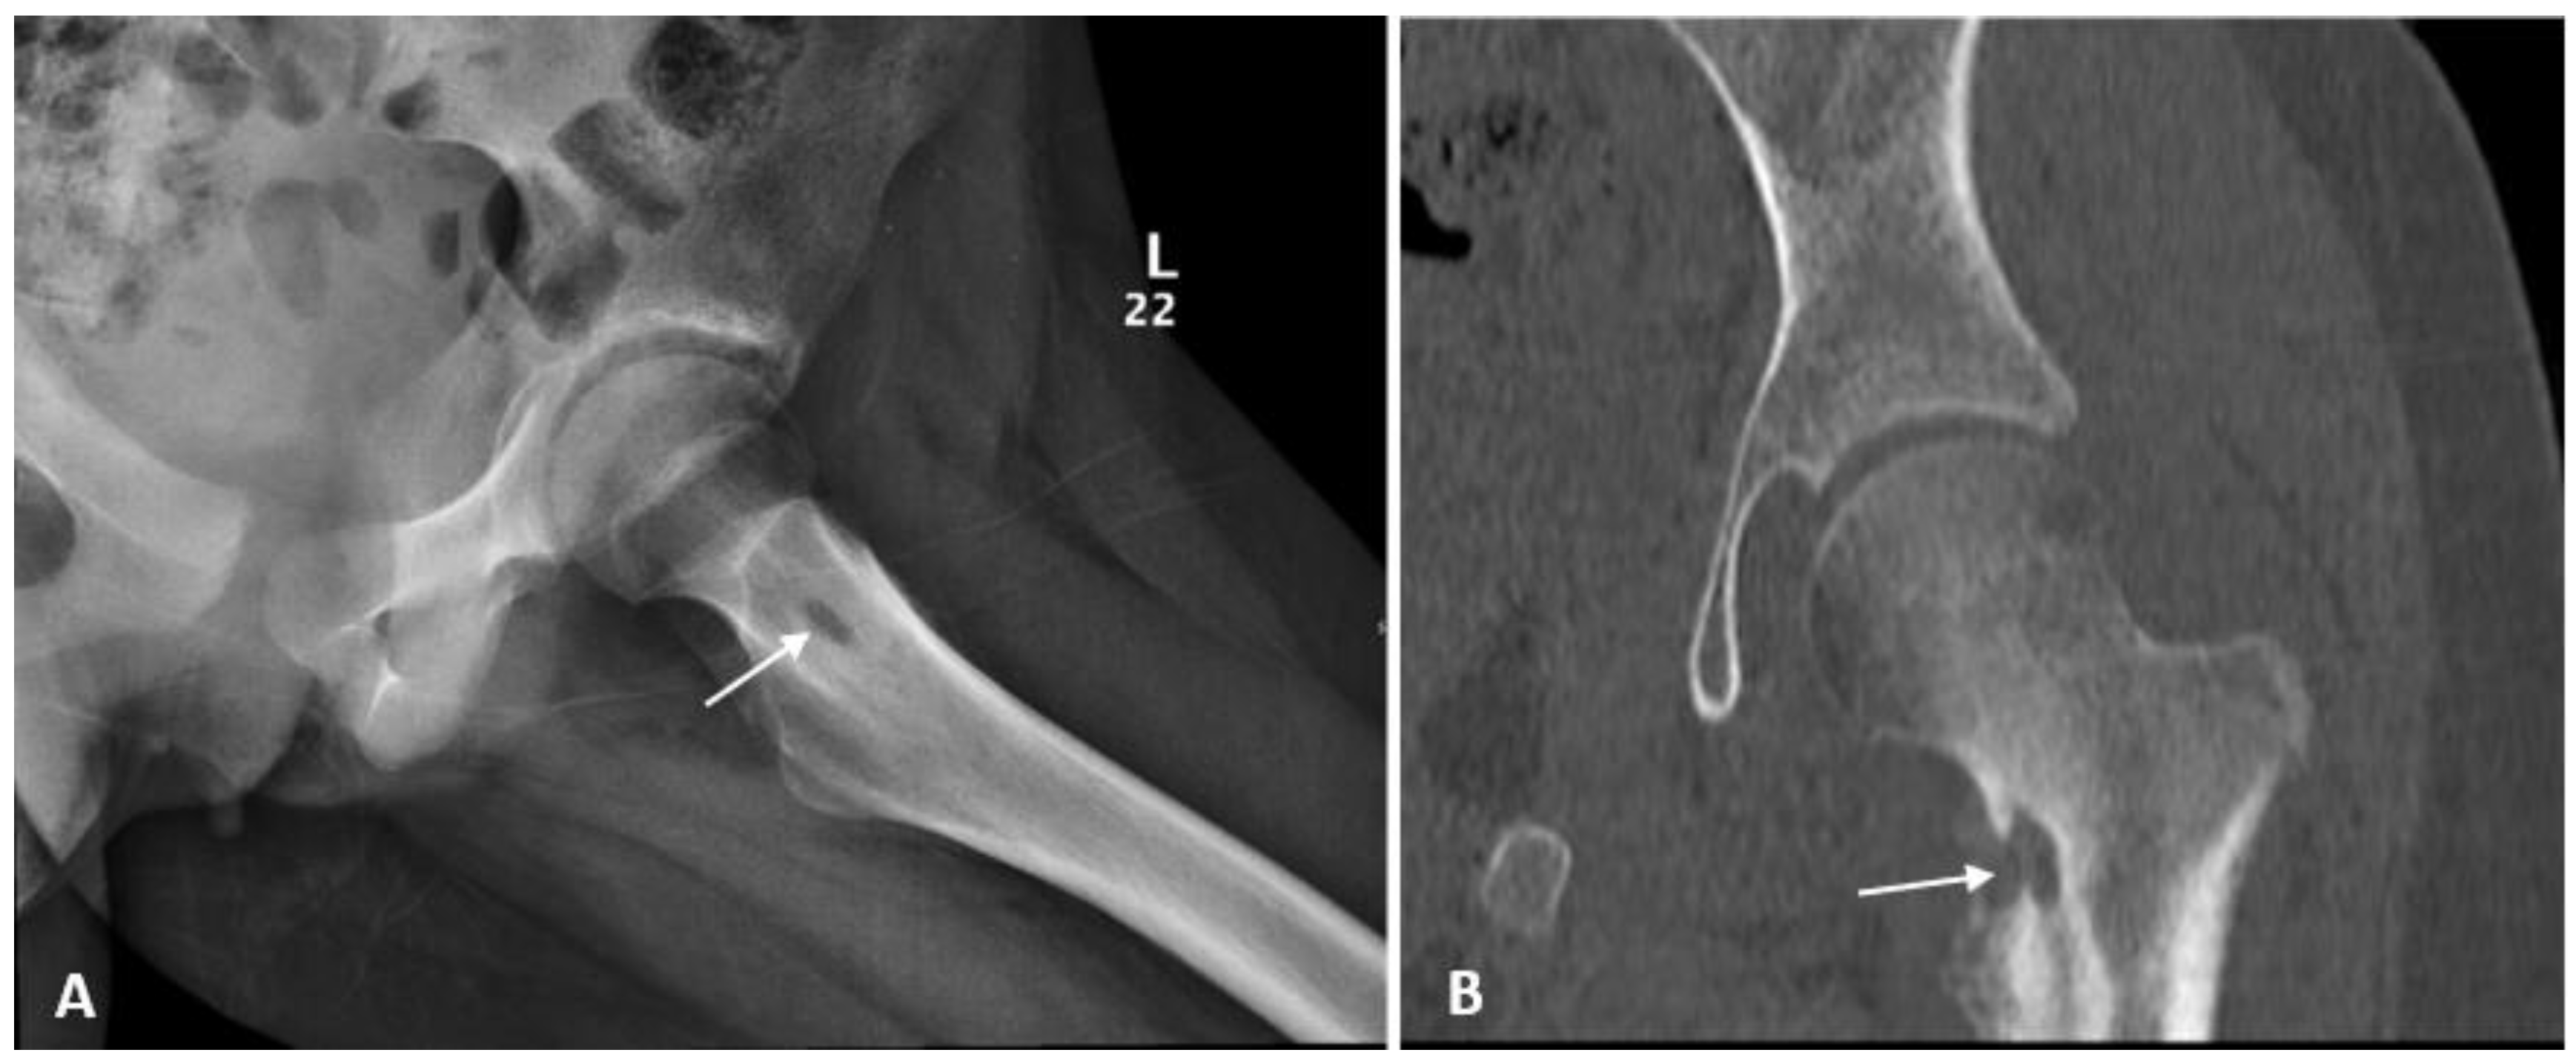

Non-specific arthritis was the preliminary diagnosis based on clinical, laboratory, and radiological findings of narrowing joint space. Follow-up plain radiograph of the affected hip showed sclerosis with central lucency at the medial aspect of the left femoral neck associated with cortical irregularity and periosteal reaction. Further evaluation by Computed Tomography (CT) scan revealed similar findings (Figure 1).

Figure 1.

(A) Hip X-ray showed increased sclerosis with central lucency at the medial aspect of left femoral neck associated with the cortical irregularity and periosteal reaction; (B) Computed Tomography (CT) scan confirmed the erosive nature of the lesion with adjacent sclerosis and the adjacent bony overgrowth.